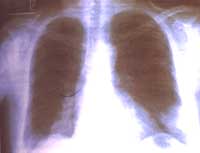

Había consultado doce días antes a otra institución donde le habían tomado radiografía de tórax (Figura 1) y le formularon tratamiento ambulatorio con Amoxicilina 500mg c/8h sin presentar mejoría de los síntomas. Refería además, debilidad y disestesias de miembros inferiores de unos cinco años de evolución, así como diaforesis profusa nocturna.

Figura No 1. Rx tórax proyección P-A inicial, Imágenes nodulares bibasales,

la del lado izquierdo, subpleural, con broncograma aéreo.

La radiografía de tórax (Figura 2) tomada en urgencias fue muy similar a la anterior.

Figura No 2. Rx tórax proyección lateral inicial.

Bajo el diagnóstico clínico de Neumonía Adquirida en la Comunidad multilobar en paciente inmuno-comprometida se inició tratamiento intrahospitalario con Clindamicina, Ciprofloxacina, obteniéndose una respuesta clínica favorable por lo que se dio de alta a los ocho días de tratamiento. Debido a la persistencia de la imagen radiológica (Figura 3) aún finalizado el tratamiento, se tomó TAC de tórax (Figuras 4A y B).

Figura No 3. Rx tórax posterior al tratamiento antibiótico.